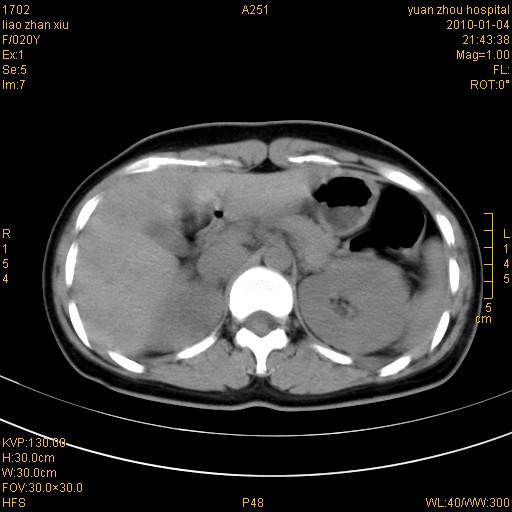

标题: CT23985:F20Y 外伤典型病例 [打印本页]

标题: CT23985:F20Y 外伤典型病例

左肾挫伤,包膜下积血。

左肾挫裂伤伴肾被膜下积血!另:肾周筋膜增厚!

1)左肾包膜下血肿。2)左侧肾挫伤可能;建议:行ct增强扫描检查。3)腰椎左侧横突骨折。

左肾挫伤,包膜下积血,l3、4左侧横突多发骨折。

双侧肾胞膜下出血,左侧较多。l3、4左侧横突多发骨折。

1、左肾挫伤,包膜下积血;

2、l3、4左侧横突多发骨折;

3、腹腔积气,考虑肠管破裂?

左肾挫伤,包膜下积血,L1、2、3、4左侧横突多发骨折。